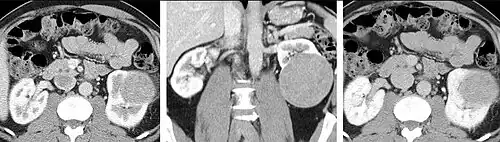

Detection and characterization of renal parenchymal masses is a frequent indication for CT. An initial noncontrast CT is important for detecting calcium or fat in a lesion, and to provide baseline attenuation of any renal masses. Following noncontrast scanning, intravenous contrast is injected and a corticomedullary phase is obtained at approximately 70 seconds (figure 7a, 7b). The corticomedullary phase is characterized by enhancement of the renal cortex as well as the renal vasculature. This phase is valuable in the evaluation of benign renal variants, lymphadenopathy and vasculature, however certain medullary renal masses may not be visible during this phase due to minimal enhancement of the medulla and collecting system. The parenchymal phase is obtained approximately 100–200 seconds after the injection of contrast material (figure 7c). Parenchymal phase imaging demonstrates continued enhancement of the cortex, enhancement of the medulla, and various levels of contrast material in the collecting system. The parenchymal phase is highly important for the detection and characterization of renal masses, parenchymal abnormalities, and the renal collecting system. This method of imaging does not evaluate for abnormalities of the collecting system.

-

FIGURE 7. Selected images from a renal mass specific protocol CT. Corticomedullary phase (axial 7a) demonstrates peripheral enhancement of the renal cortex with minimal opacification of the renal medulla. There is a large renal cell carcinoma in the left kidney (right in image) which can be differentiated from the normal renal parenchyma by the heterogeneous and differential enhancement. The renal artery and vein are opacified in this phase as well. The collecting system is not opacified (coronal reformat 7b). In the parenchymal phase, the renal cortex and the medulla are enhancing. The renal cell carcinoma in the left kidney is not as well defined when compared to the corticomedullary phase images, but is actually slightly more conspicuous. There is some contrast noted within the collecting system during this phase (7c).